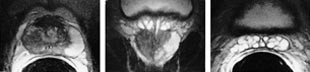

Fremstilling og differensiering av ulike typer normalt og patologisk vev i prostata krever bruk av både T1- og T2-vektede bilder. I en oversiktsartikkel av Schiebler og medarbeidere i Radiology i 1993 (11) er det en detaljert beskrivelse av de ulike signalmønstrene; noen av de viktigste er vist i tabell 2. Et T1-vektet bilde vil vise prostatakjertelen og sædblæren som homogene strukturer med intermediær og lav signalintensitet. Et T2-vektet bilde vil differensiere mellom den perifere sone (høy signalintensitet) og overgangssonen (lav signalintensitet) og vise svært høy signalintensitet i de væskefylte tubulære hulrommene i sædblærene (fig 2).

Prostatakreft oppstår oftest i den perifere sonen (70 %), mens prostatahyperplasien har sitt utgangspunkt i overgangssonen. Hyperplasi i overgangssonen komprimerer ofte den perifere sone, og dette vises i de T2-vektede bildene. Prostatakreft og biopsihematom er etter vår erfaring de hyppigste årsakene til hypointense prosesser i den perifere sone på T2-vektede bilder. T1-vektede bilder vil differensiere mellom disse to årsakene idet hematomet er hyperintenst og prostatakreft er isointenst. Det bør gå minst tre uker mellom biopsi og en MR-undersøkelse av prostata.